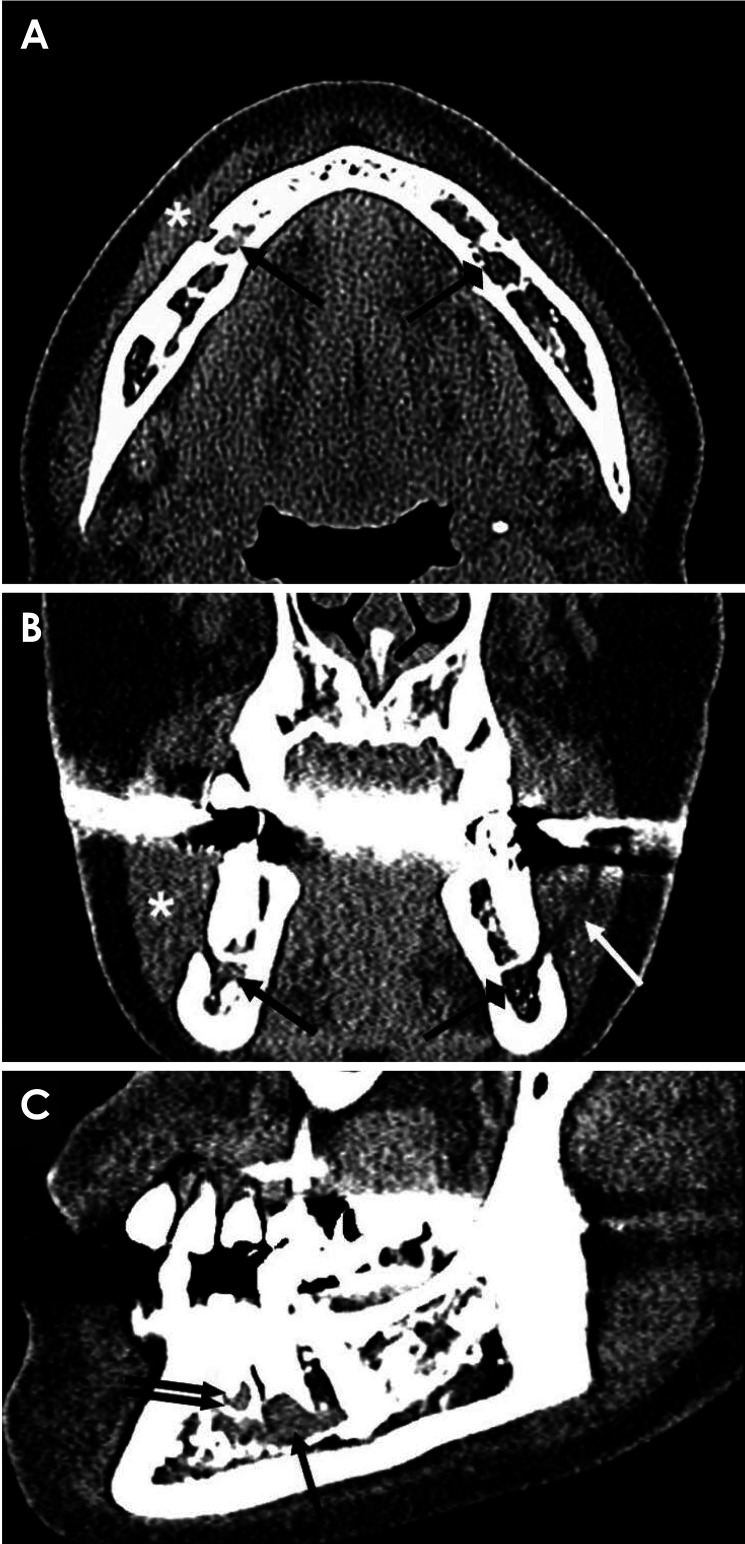

Components derived from an infected lesion within the bone can spread through various passages in the mandible, particularly via the mental foramen. Radiologically, the spread of infection is typically nonspecific and challenging to characterize; however, multislice computed tomography (MSCT) can effectively detect pathological changes in soft tissues and the bone marrow space. This report describes the case of a 55-year-old woman who experienced mental nerve paresthesia due to a periapical infection of the right mandibular second premolar. MSCT imaging revealed increased attenuation around the periapical lesion extending into the mandibular canal and loss of the juxtamental foraminal fat pad. Following endodontic treatment of the tooth suspected to be the source of the infection, the patient's symptoms resolved, and the previous MSCT imaging findings were no longer present. Increased bone marrow attenuation and obliteration of the fat plane in the buccal aspect of the mental foramen may serve as radiologic indicators of inflammation spreading from the bone marrow space.